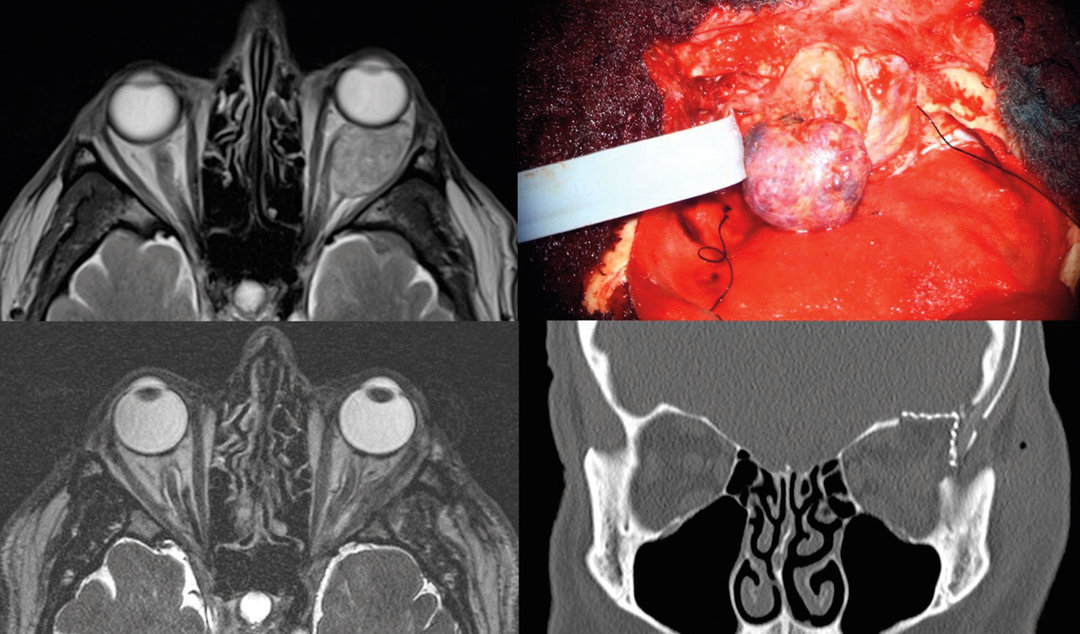

Auch Metastasen von zum Beispiel Mammakarzinomen führen zu Raumforderungen in der Orbita, welche es zu entfernen gilt. Auch Metastasen von zum Beispiel Mammakarzinomen führen zu Raumforderungen in der Orbita, welche es zu entfernen gilt. © Schmidt L et al. Wehrmedizinische Monatsschrift 2021; 65: 199-205 © Beta Verlag & Marketinggesellschaft mbH, Bonn

2009 wurde bei einem 71-Jährigen erstmalig ein links retrobulbär gelegenes kavernöses Hämangiom entdeckt. Auch in diesem Fall entschied man sich nicht direkt zu operieren. Seit 2018 wuchs es allerdings stetig und hatte nun zu Exophthalmus und Trockenheit des Auges geführt (s. Abb. 3).

Der Mann gab jetzt auch gelegentliche Doppelbilder und Motilitätsstörungen des Bulbus an. Daher fiel die Entscheidung zur Resektion, die unter Zusammenarbeit von Neuro- und Mund-Kiefer-Gesichts­chirurgen vollständig gelang. Die Rekonstruktion der Orbita war dann wieder Sache des MKG-Teams. Die Protrusio bildete sich inzwischen vollständig zurück, der Mann ist beschwerdefrei.